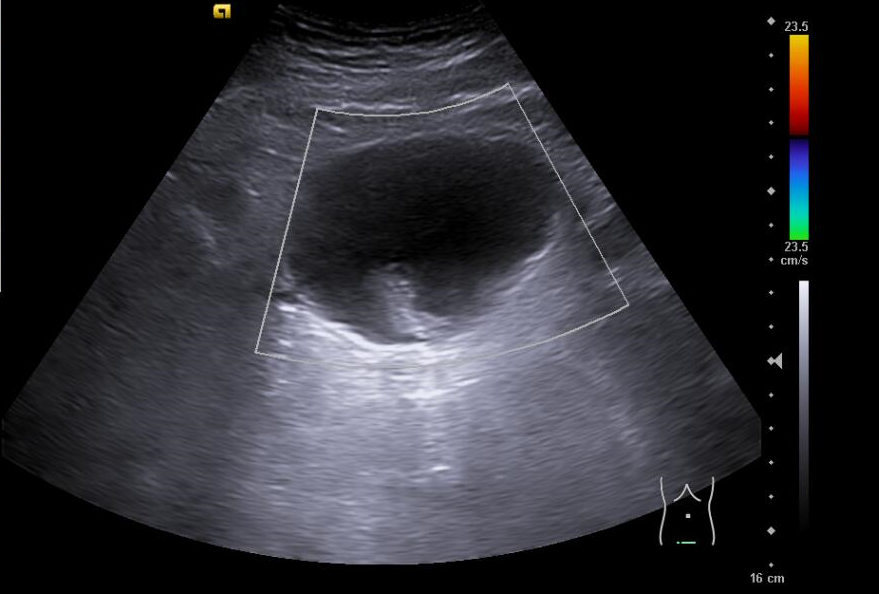

En ecografía clínica de aparato urinario se objetiva a nivel de vejiga imagen hiperecogénica dependiente de pared que no se moviliza con la movilización del paciente y no capta con modo Doppler color.

Ecografía aparato urinario agosto 2024: Litiasis en cáliz medio izquierdo de 6 mm, lesiones vesicales, próstata de 45 g.

Cistoscopia agosto 2024: Descripción de hallazgos vesicales: Lesión papilo-sólida en fondo vesical con calcificaciones en su superficie, de aproximadamente 1-1,5 cm de tamaño.